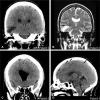

Objectives This study is aimed to report the largest independent case series of spontaneous otogenic pneumocephalus (SOP) and review its pathophysiology, clinical presentation, and treatment. Design Four patients underwent a middle cranial fossa approach for repair of the tegmen tympani and tegmen mastoideum. A comprehensive review of the literature regarding this disease entity was performed. Setting U.S. tertiary academic medical center. Participants: Patients presenting to the lead author's clinic or to the emergency department with radiographic evidence of SOP. Symptoms included headache, otalgia, and neurologic deficits. Main Outcome Measures Patients were assessed for length of stay, postoperative length of stay, and neurologic outcome. Three of four patients returned to their neurologic baseline following repair. Results Four patients were successfully managed via a middle cranial fossa approach to repairing the tegmen mastoideum. Conclusion The middle cranial fossa approach is an effective strategy to repair defects of the tegmen mastoideum. SOP remains a clinically rare disease, with little published information on its diagnosis and treatment.